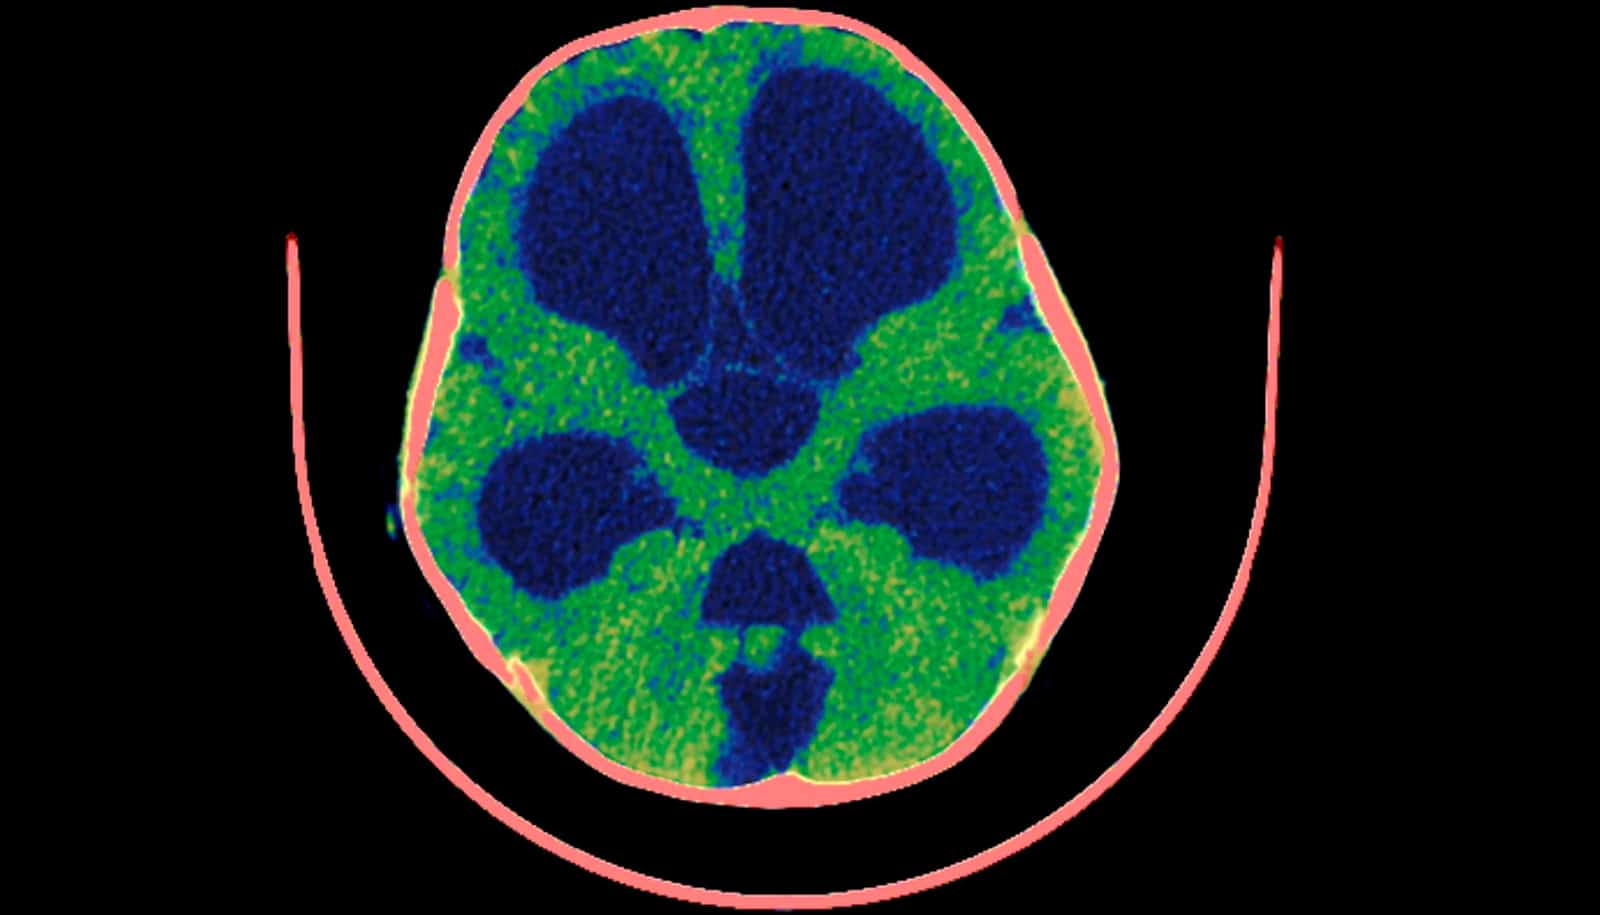

Discovery may upend ideas about the cause of hydrocephalus

"We showed that the conventional understanding of the cause of hydrocephalus is not correct."